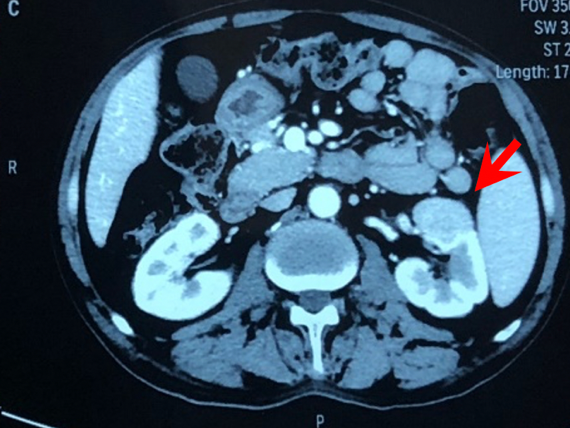

● 肾穿刺活检

图3:肾穿刺活检

● 痰标本、肾穿刺活检组织送检二代测序提示伞枝横梗霉